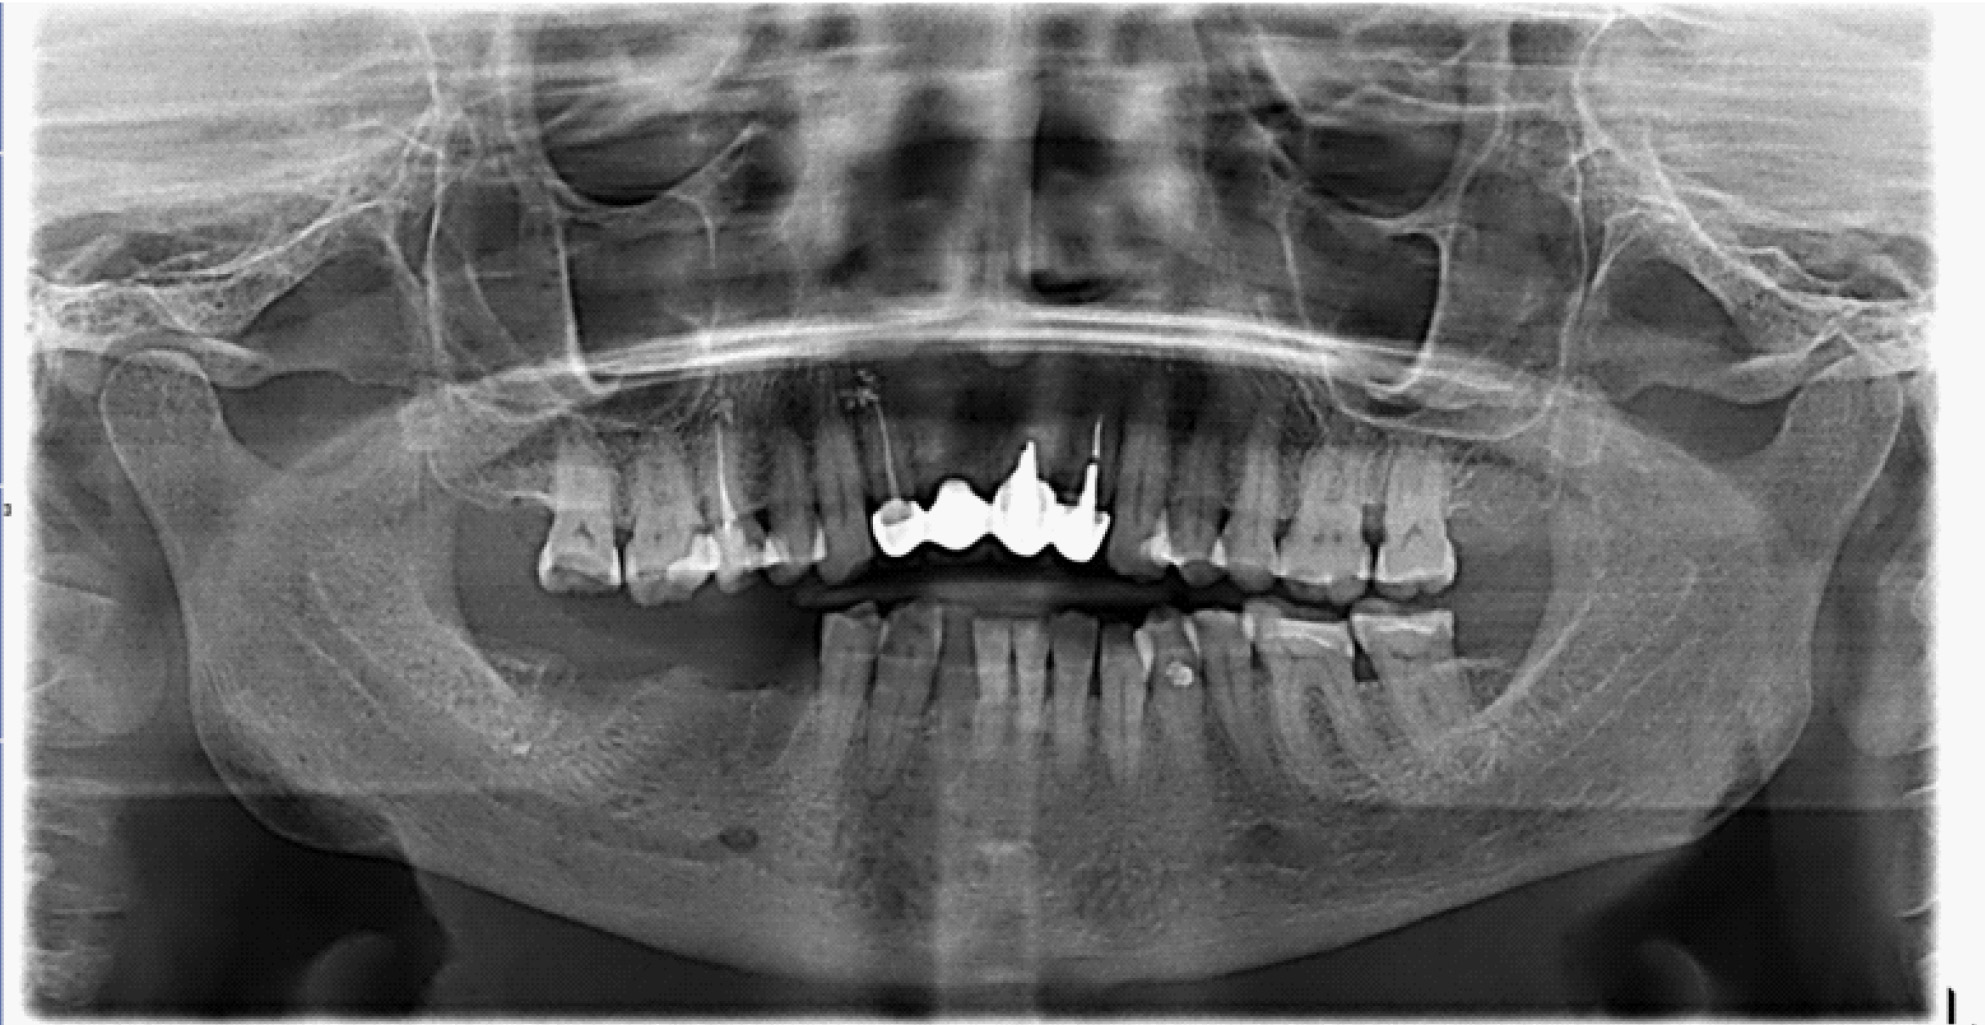

В настоящее время выделяют два основных подхода к лечению БФОНЧ, к ним относятся консервативный и хирургический подход. Выбор тактики лечения пациента зависит от стадии заболевания. Консервативное лечение предусматривает назначение пациентам курсовой антибактериальной, симптоматической терапии препаратов для улучшения микроциркуляции, ежедневной обработки очагов поражения костной ткани растворами антисептиков, частичная некроэктомия, удаление подвижных секвестров, а также тщательное соблюдение гигиены полости рта (рис. 4).

Рис. 4. Компьютерно-томографическое исследование на этапе лечения остеонекроза нижней челюсти справа у пациентки Б. в 2023 г.

За период лечения пациентки Б. было выполнено хирургическое лечение в следующем объеме: кюретаж лунок удаленных зубов, частичная секвестрэктомия, резекция альвеолярной части нижней челюсти справа, вскрытие и дренирование гнойных очагов в стадии обострения патологического процесса. Отмечалось улучшение клинической и рентгенологической картины в полости рта (рис. 5, 6).

Рис. 5. Клинические проявления бисфосфонатного остеонекроза нижней челюсти справа у пациентки Б. в 2024 году

Рис. 6. Ортопантомограмма на этапе лечения остеонекроза нижней челюсти справа у пациентки Б. в 2024 г.